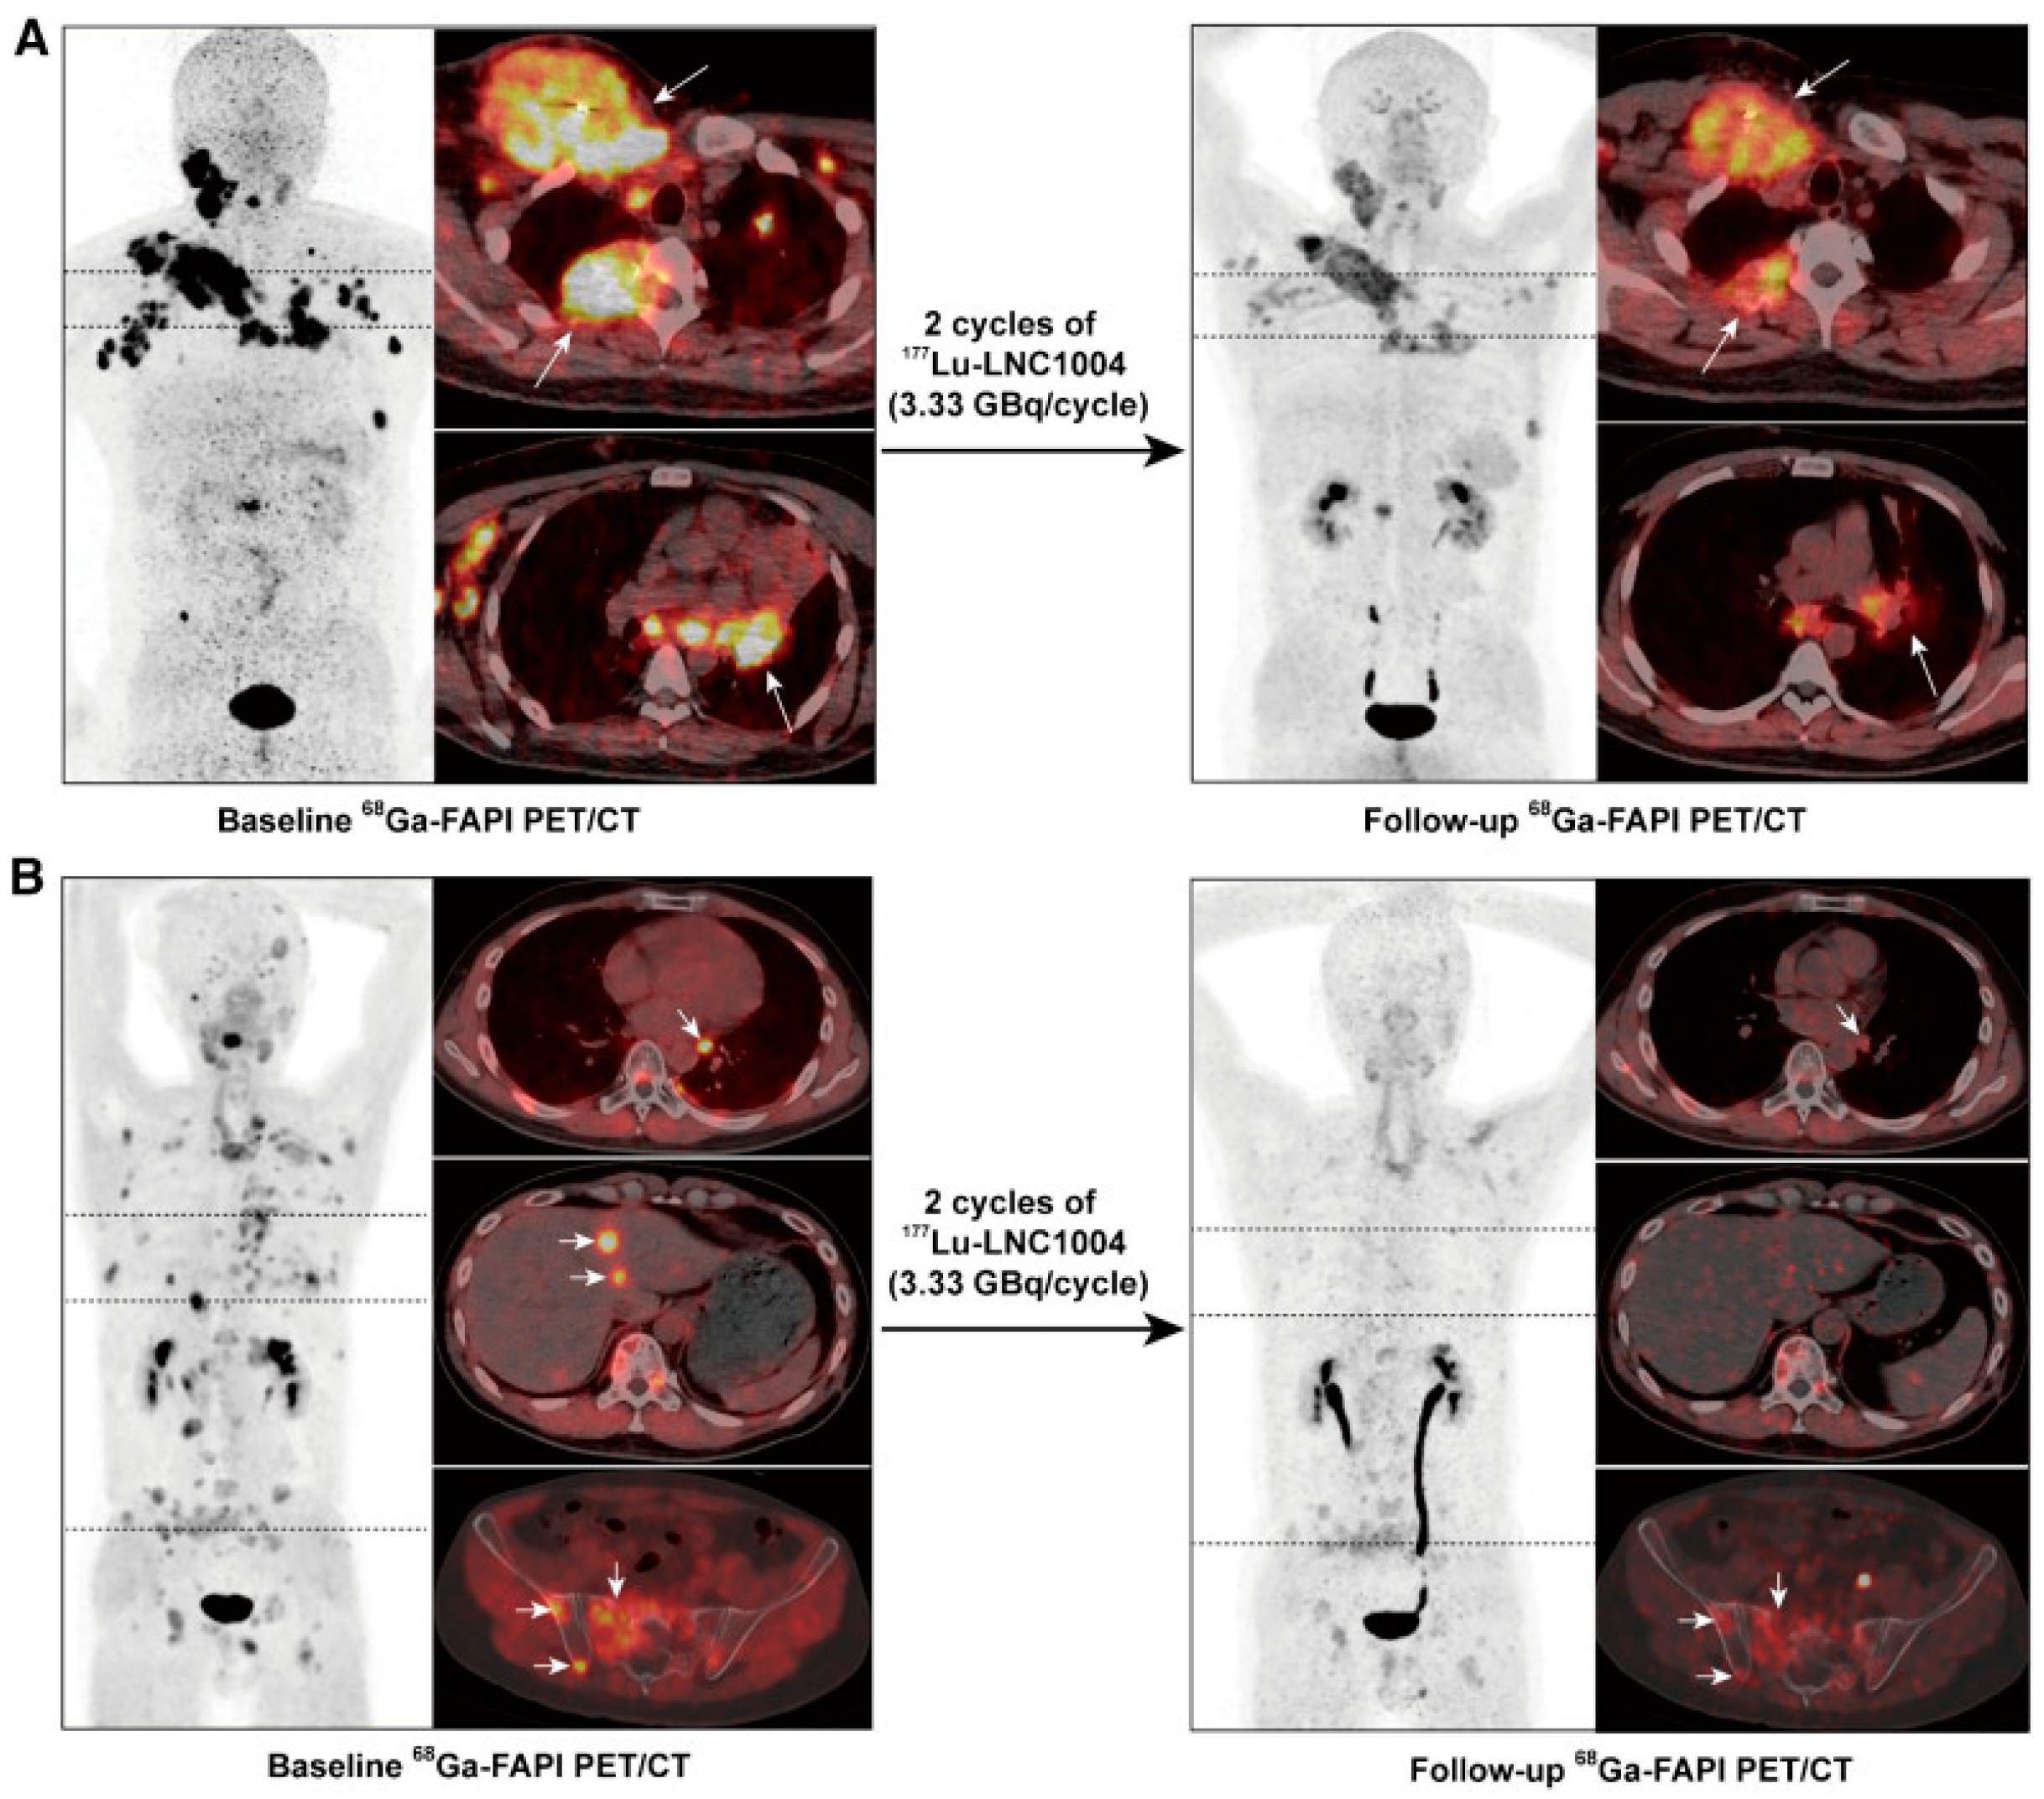

- Fu, H.; Huang, J.; Zhao, L.; Chen, Y.; Xu, W.; Cai, J.; Yu, L.; Pang, Y.; Guo, W.; Su, B.; et al. 177Lu-LNC1004 Radioligand Therapy in Patients with End-Stage Metastatic Cancers: A Single-Center, Single-Arm, Phase II Study. Clin. Cancer Res. 2025, 31, 1415. [Google Scholar] [CrossRef] [PubMed]

| Fu et al. (2023) [19] | 6 weeks after second cycle | 2 | Bone metastases: 5.12 Metastatic lymph nodes: 5.95 Other metastases: 15.27 Kidneys: 1.32 Bone marrow: 0.11 | NR | PR: 3/12 (25%) SD: 7/12 (58%) PD: 2/12 (17%) | NR | NR |

| Fu et al. (2025) [47] | 18.1 months | 2 | Primary tumor lesions: 4.69 Bone metastases: 4.57 Metastatic lymph nodes: 4.88 Lung metastases: 6.47 Other metastases: 3.77 | NR | PR: 4/20 (20%) 2 SD: 9/20 (45%) 2 PD: 7/20 (35%) 2 | NR | 4 (6.3) |

| [177Lu]Lu-EB-FAPI | Albumin-binding small molecule | Prolonged tumor uptake up to 7 days in the dose-escalation study and up to ≈2 weeks in the expanded cohort; longer effective half-life in bone metastases than in lymph nodes and other lesions. Effective blood half-life (0.21 ± 0.11 h, half-life α; 68.01 ± 26.69 half-life β). | Primary lesions: 4.69 ± 3.83; bone metastasis: 4.57 ± 1.98; lymph node metastasis: 4.88 ± 4.39; lung metastases: 6.47 ± 6.75; other metastases: 3.77 ± 1.74. | Fu et al. [47] Wang et al., 2025 [60] |